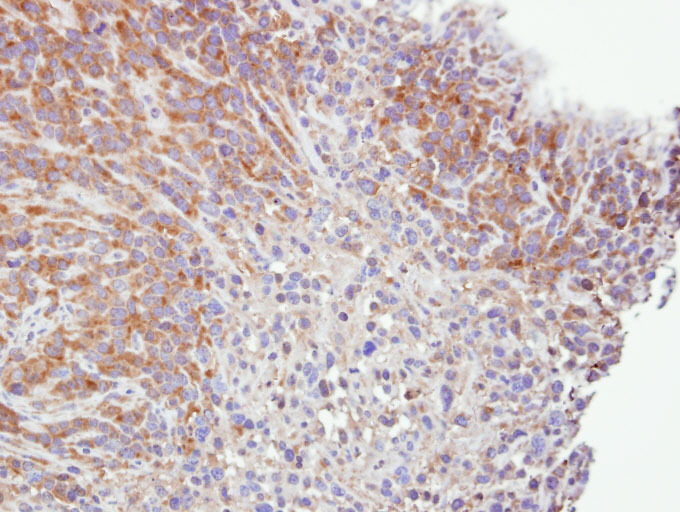

- Immunohistochemical analysis of paraffin-embedded SAS xenograft, using Caspase 4 antibody at 1: 500 dilution.